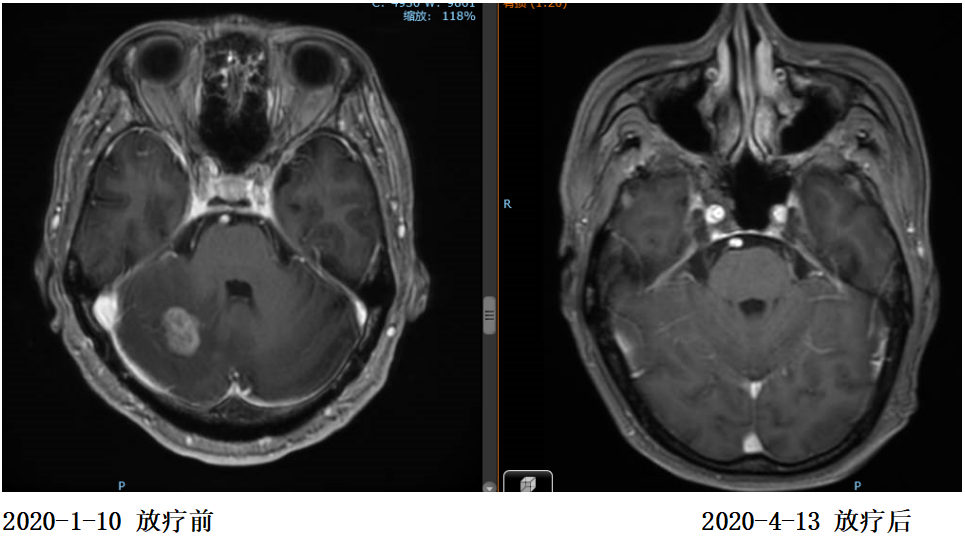

2020年1月13日开始对左侧枕叶及右侧小脑转移灶进行放疗,PTV-GTV=44.5Gy/9F

复查:2020.4复查颈部CT及全腹部+盆腔MR大致同前,脑MR示病变较前明显缩小,评估PR。